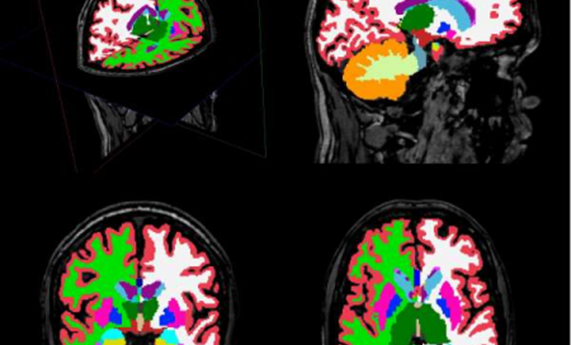

Describen alteraciones en estructuras cerebrales en pacientes con esquizofrenia descubiertas mediante un innovador análisis de imagen cerebral

14/07/2015